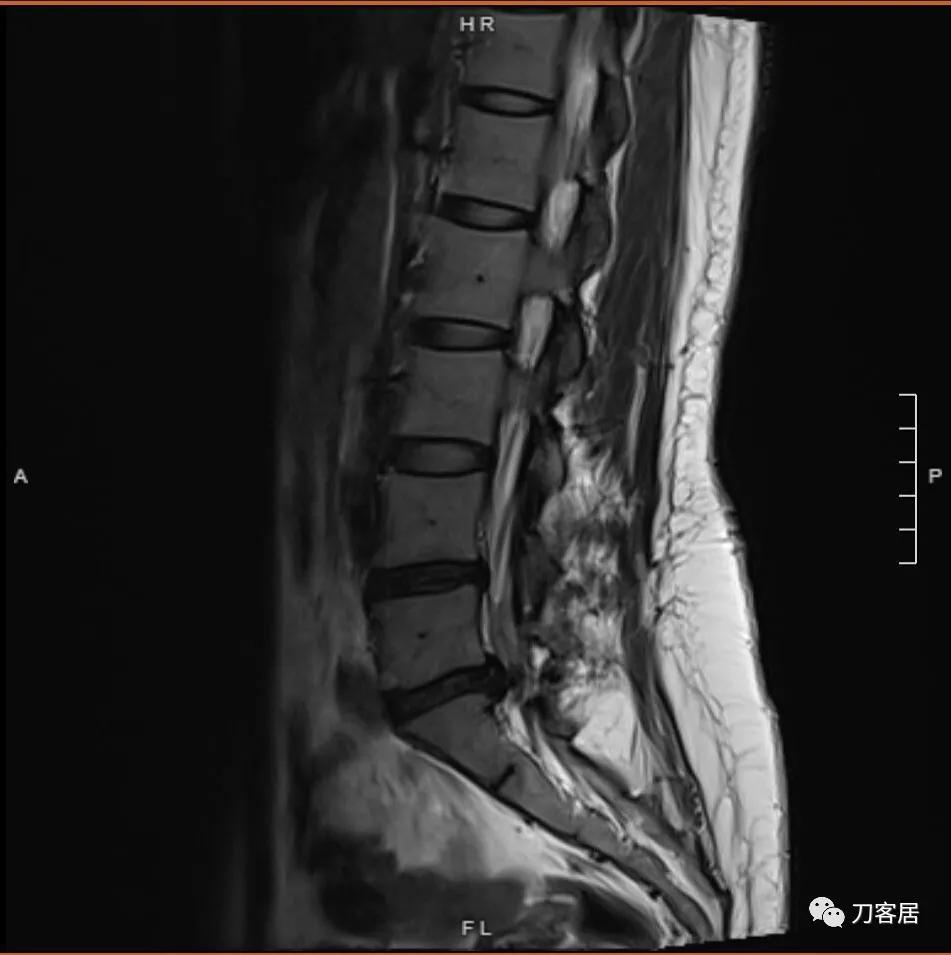

以下是患者的影像资料:

图1. 微创术前腰椎MRI矢状面T2相,提示腰5骶1椎间盘突出,腰4-骶1椎体对应平面后方软组织结构紊乱,应该是以前做过手术。